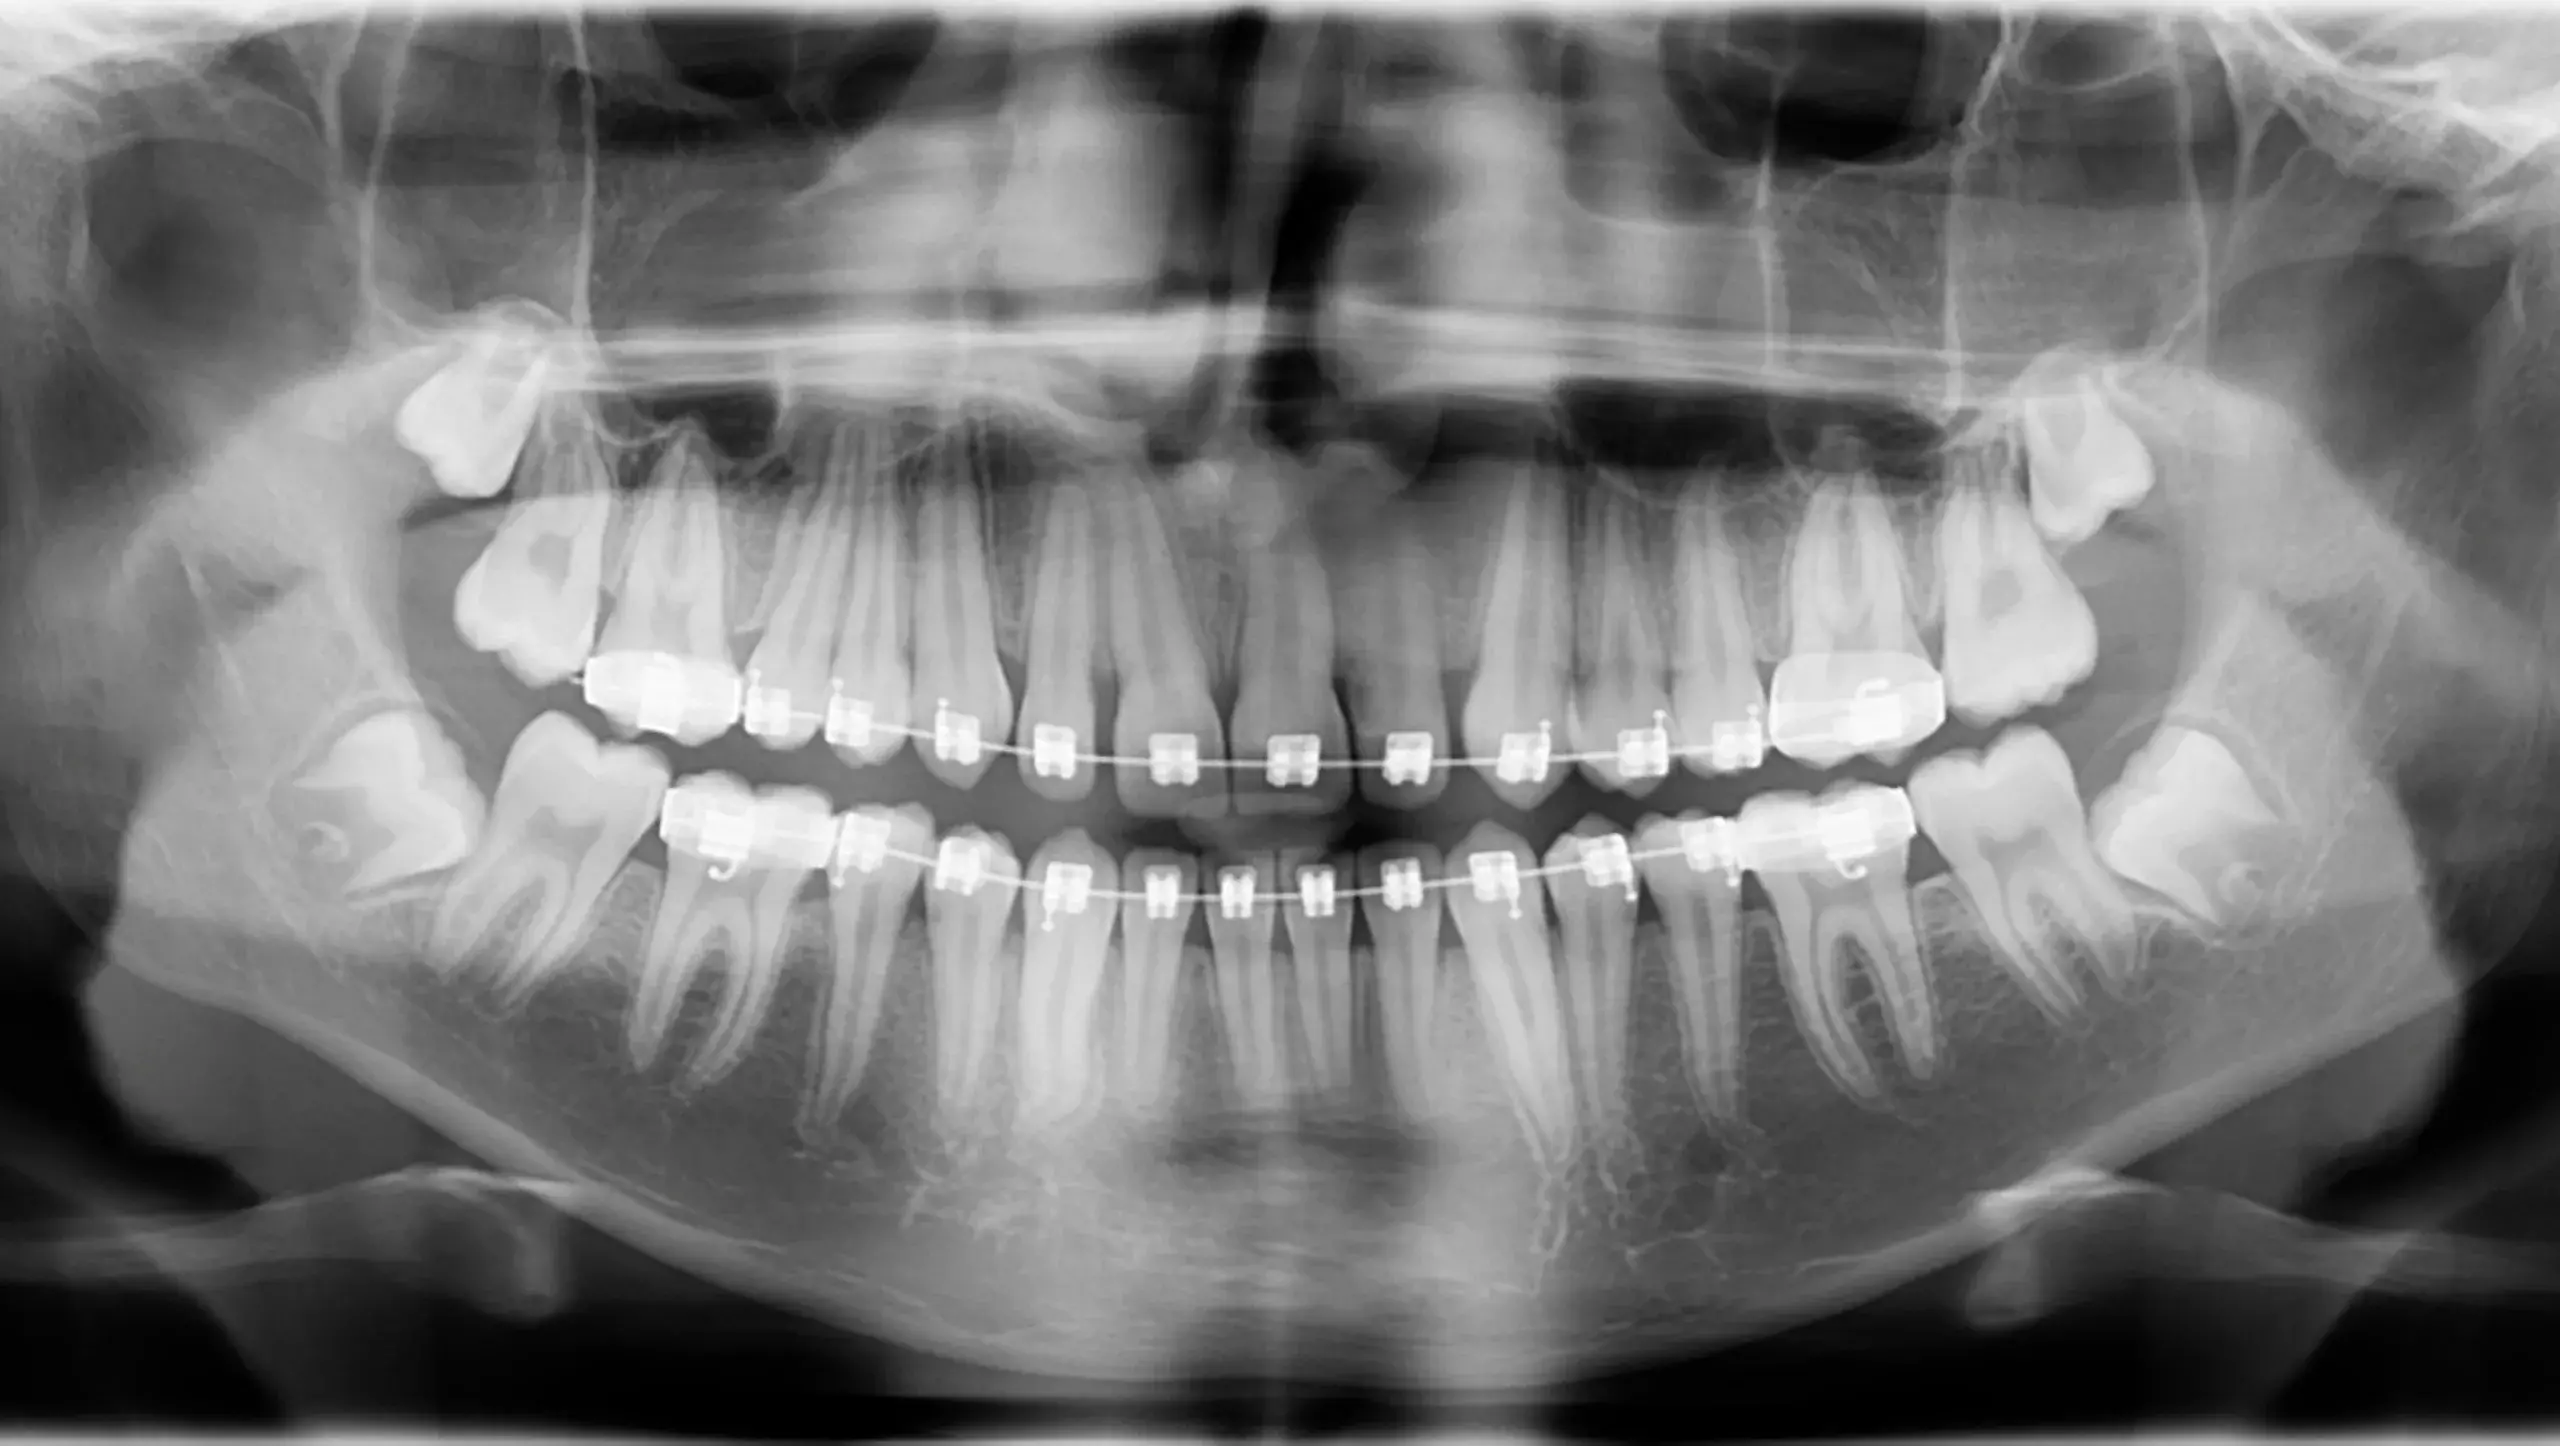

Caso clínico 5: Canino inferior incluido

Caso clínico 5: Canino inferior incluido El diagnóstico principal para este caso fue un canino inferior impactado.Antes de la ortodoncia:Canino impactado:El canino inferior derecho no había erupcionado en su posición…